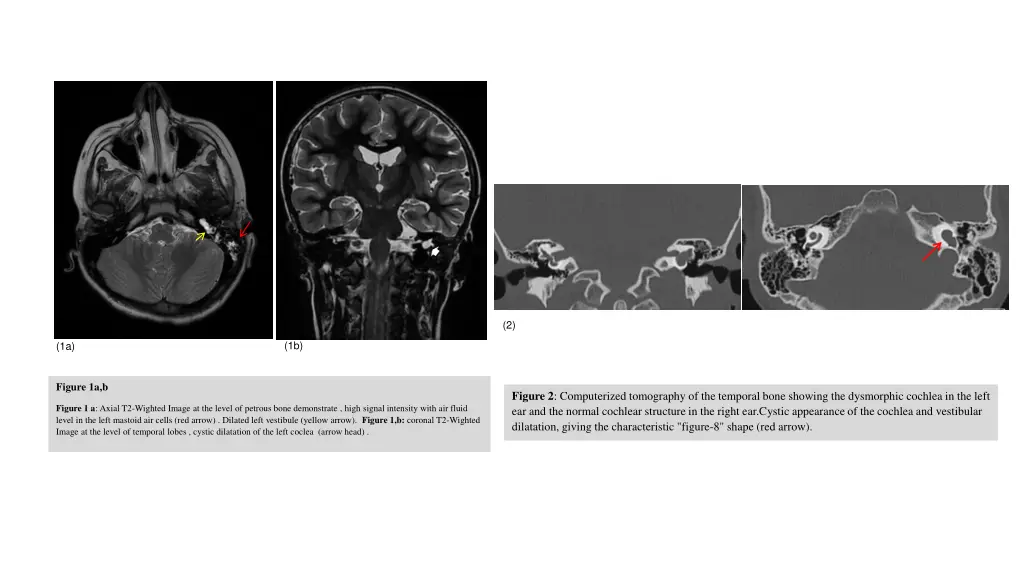

Case Report Case Report A 9-year-old girl was referred to the Royal Hospital with a history of recurrent meningitis. Cerebrospinal fluid (CSF) polymerase chain reaction (PCR) testing confirmed Streptococcus pneumoniae and Haemophilus influenzae as the causative pathogens. The first episode occurred at the age of 7, followed by a second episode in December 2023 and the most recent in January 2024. Clinical evaluation revealed sensorineural hearing loss and otitis media with effusion in the left ear. The patient was treated with a three-week course of intravenous antibiotics and was discharged after full recovery. Magnetic resonance imaging (MRI) of the brain (Figures 1a, b) demonstrated left-sided mastoiditis and abnormalities in the temporal bone anatomy. Specifically, the cochlea appeared cystic, with an absent modiolus (Figure 1b). There was no definitive basal turn of the cochlea, and the vestibular aqueduct was markedly dilated, measuring approximately 1.6 mm (Figure 1a). These findings strongly indicated a congenital inner ear malformation consistent with incomplete cochlear partition type 1 (ICP-1). To confirm the diagnosis, high-resolution computed tomography (HRCT) of the temporal bone was performed. The imaging revealed the characteristic "figure-8" appearance of the cochlea, confirming its cystic configuration and vestibular dilatation (Figures 2a, b). Additionally, the semicircular canals were found to be dysplastic and smaller than normal, further supporting the diagnosis of Mondini dysplasia.

(2) (1b) (1a) Figure 1a,b Figure 2: Computerized tomography of the temporal bone showing the dysmorphic cochlea in the left ear and the normal cochlear structure in the right ear.Cystic appearance of the cochlea and vestibular dilatation, giving the characteristic "figure-8" shape (red arrow). Figure 1 a: Axial T2-Wighted Image at the level of petrous bone demonstrate , high signal intensity with air fluid level in the left mastoid air cells (red arrow) . Dilated left vestibule (yellow arrow). Figure 1,b: coronal T2-Wighted Image at the level of temporal lobes , cystic dilatation of the left coclea (arrow head) .